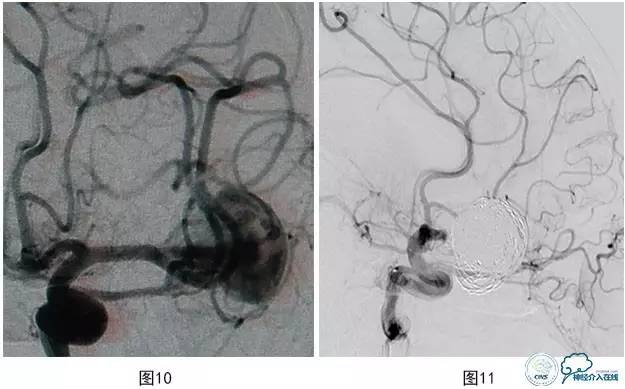

病例3:患者男,27岁。头痛2个月,左大脑中动脉M2段上干起始部靠近分叉部位巨大动脉瘤,下干起始部靠近瘤颈(图10),行支架辅助栓塞治疗,保护下干。术中载瘤动脉闭塞(图11),弹簧圈突入支架内(图12)。

图10 左MCA M2段上干起始部靠近分叉部位巨大动脉瘤

图11 载瘤动脉闭塞

图12 弹簧圈突入载瘤动脉支架内-血管急性闭塞

图13将微导管超选入载瘤动脉注入替罗非班10ml